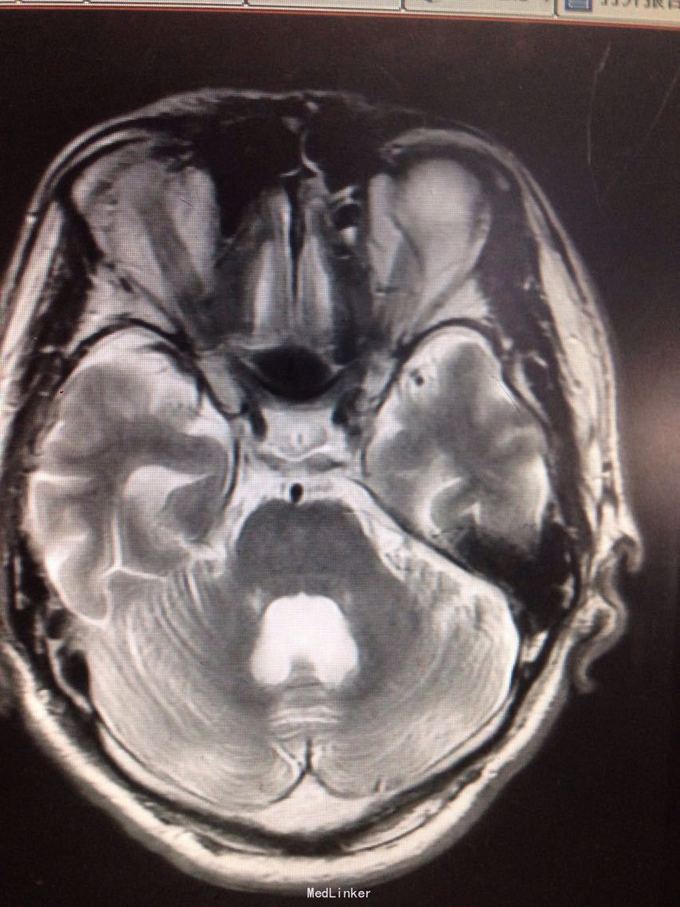

查体可见右手3、4、5指肌力3级,余肢体肌力5级。四肢腱反射减弱。 颅脑MR提示:右侧中央前回皮层下亚急性腔梗,脑萎缩,脑白质变性。 糖化血红蛋白8.2%。